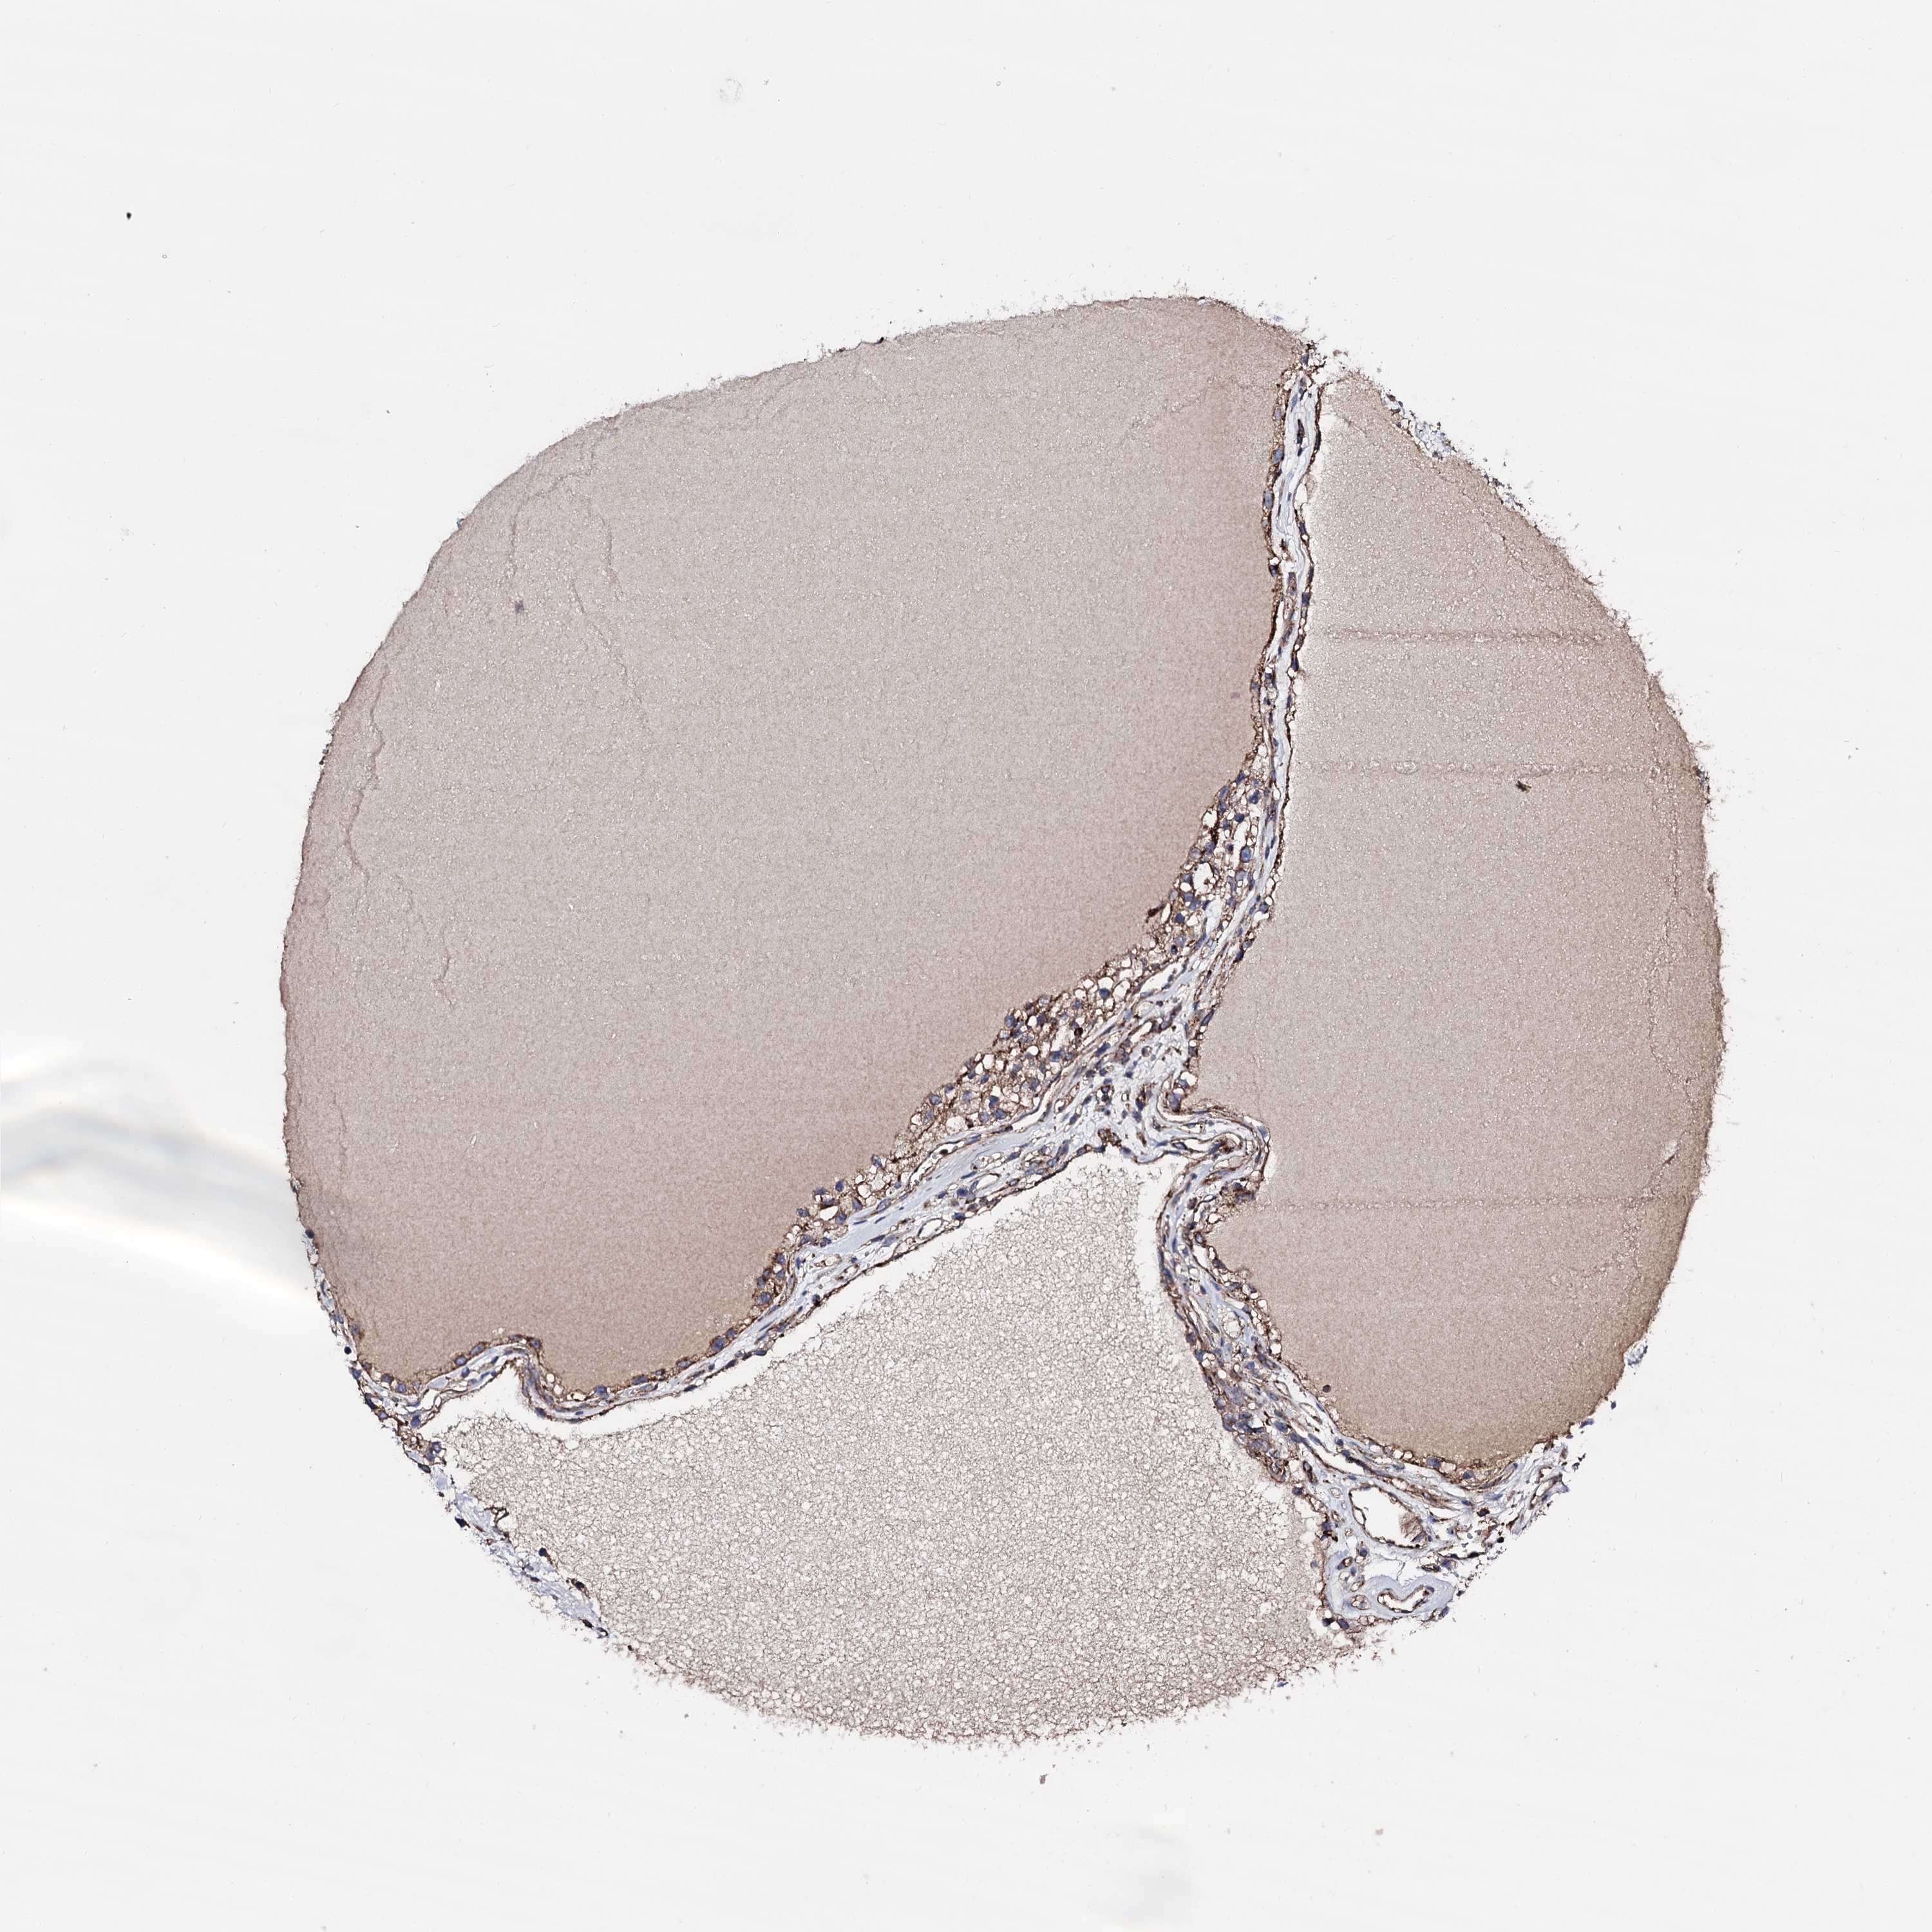

KIDNEY RENAL PAPILLARY CELL CARCINOMA (TCGA) - Interactive survival scatter ploti

The Survival Scatter plot shows the clinical status (i.e. dead or alive) for all individuals in the patient cohort, based on the same data that underlies the corresponding Kaplan-Meier plots. Patients that are alive at last time for follow-up are shown in blue and patients who have died during the study are shown in red.

The x-axis shows the expression levels (FPKM) of the investigated gene in the tumor tissue at the time of diagnosis. The y-axis shows the follow-up time after diagnosis (years). Both axes are complimented with kernel density curves demonstrating the data density over the axes. The top density plot shows the expression levels (FPKM) distribution among dead (red) and alive patients (blue). The right density plot shows the data density of the survived years of dead patients with high and low expression levels respectively, stratified using the cutoff indicated by the vertical dashed line through the Survival Scatter plot. This cutoff is automatically defined based on the FPKM cutoff that minimizes the p-score. The cutoff can be changed by dragging the vertical line or by entering a cutoff value in the square labeled "Current cut-off".

Under the Survival Scatter plot the p-score landscape (black curve; left axis) is shown together with dead median separation (red curve; right axis). Dead median separation is the difference in median mRNA expression between patients who have died with high and low expression, respectively. It is calculated as follows: median FPKM expression of dead patients with high expression - median FPKM expression of dead patients with low expression. This is intended to aid the user in visually exploring custom cutoffs and the associated p-scores and dead median separation.

Individual patient data is displayed and can be filtered by clicking on one or more of the category buttons on the top of the page. Categories describing expression level and patient information include: high, low, alive, dead, female, male and tumor stages. The scale of the x-axis can be toggled between linear and log-scale by clicking on the "x log" button. Mouse-over function shows TCGA ID, patient information and mRNA expression (FPKM) for each patient.

& Survival analysisi

Kaplan-Meier plots summarize results from analysis of correlation between mRNA expression level and patient survival. Patients were divided based on level of expression into one of the two groups "low" (under cut off) or "high" (over cut off). X-axis shows time for survival (years) and y-axis shows the probability of survival, where 1.0 corresponds to 100 percent.

IQCH is potential prognostic, high expression is favorable in Kidney Renal Papillary Cell Carcinoma (TCGA)

Best expression cut offi

Based on the FPKM value of each gene, patients were classified into two groups and association between prognosis (survival) and gene expression (FPKM) was examined. The best expression cut-off refers the FPKM value that yields maximal difference with regard to survival between the two groups at the lowest log-rank P-value. Best expression cut-off was selected based on survival analysis .

When clicking on this number, the vertical dashed line indicating cut-off, the interactive survival plot, and the Kaplan-Meier curve will be adjusted to show results based on the best expression cut-off.

: 2.08